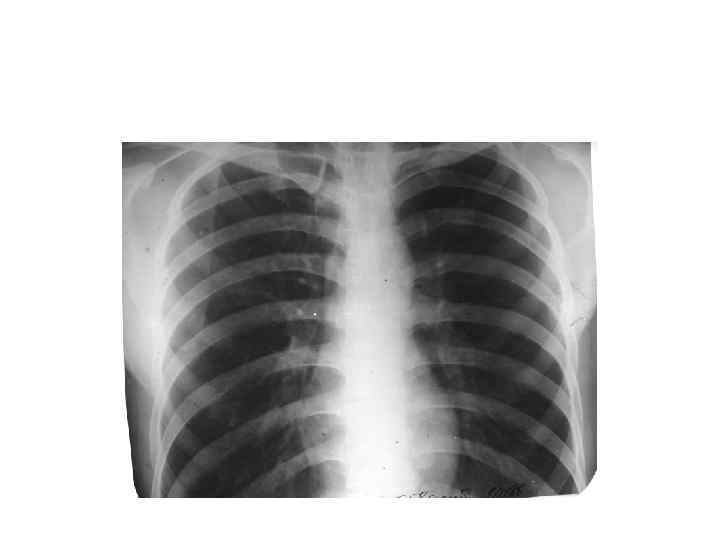

Рентгеноанатомиялық анализ

Жүрек өлшемі

нормостеник

астеник

гиперстеник